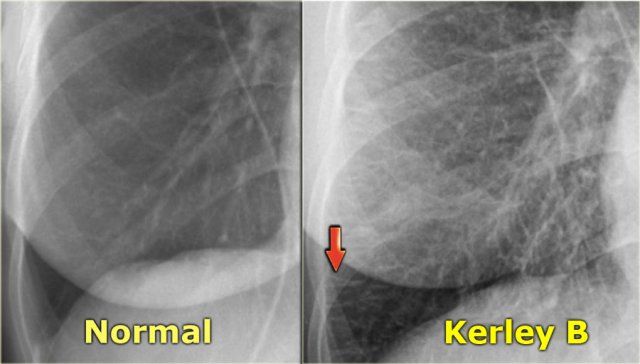

LEFT: normal. RIGHT: CHF stage II with Kerley B-lines due to interstitial edema LEFT: normal. RIGHT: CHF stage II with Kerley B-lines due to interstitial edema

Stage II - Interstitial edema

Stage II of CHF is characterized by fluid leakage into the interlobular and peribronchial interstitium as a result of the increased pressure in the capillaries.

When fluid leaks into the peripheral interlobular septa it is seen as Kerley B or septal lines.

Kerley-B lines are seen as peripheral short 1-2 cm horizontal lines near the costophrenic angles.

These lines run perpendicular to the pleura.